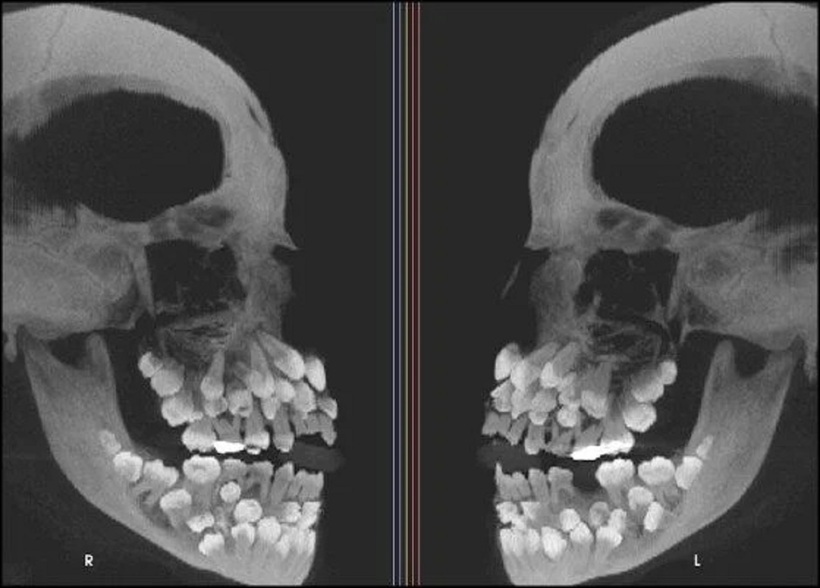

Ban đầu, bệnh nhi tìm đến phòng khám nha khoa với một yêu cầu đơn giản: nhổ một chân răng sữa còn sót lại ở hàm trên. Tuy nhiên, kết quả chụp X-quang toàn cảnh (panorama) sau đó đã khiến đội ngũ y bác sĩ vô cùng kinh ngạc. Phim chụp cho thấy một bức tranh phức tạp với tổng cộng 81 chiếc răng, bao gồm 18 răng sữa, 32 răng vĩnh viễn (tương đương bộ răng đầy đủ của một người trưởng thành) và một số lượng đáng kinh ngạc lên tới 31 răng thừa, hay còn gọi là răng siêu thừa (supernumerary teeth).

Bé gái 11 tuổi có 81 chiếc răng trong miệng. Ảnh: Ajodo

Để có được chẩn đoán chính xác và lập kế hoạch điều trị, các bác sĩ đã tiến hành chụp cắt lớp vi tính chùm tia hình nón (CBCT). Kỹ thuật này cho phép xác định vị trí ba chiều và hình thái của từng chiếc răng, đồng thời đánh giá mối tương quan của chúng với các cấu trúc giải phẫu quan trọng. Song song đó, một loạt các xét nghiệm đã được thực hiện để loại trừ khả năng bé gái mắc các hội chứng thường đi kèm với tình trạng đa răng như sứt môi hở hàm ếch, loạn sản xương đòn sọ (cleidocranial dysplasia) hay hội chứng Gardner.